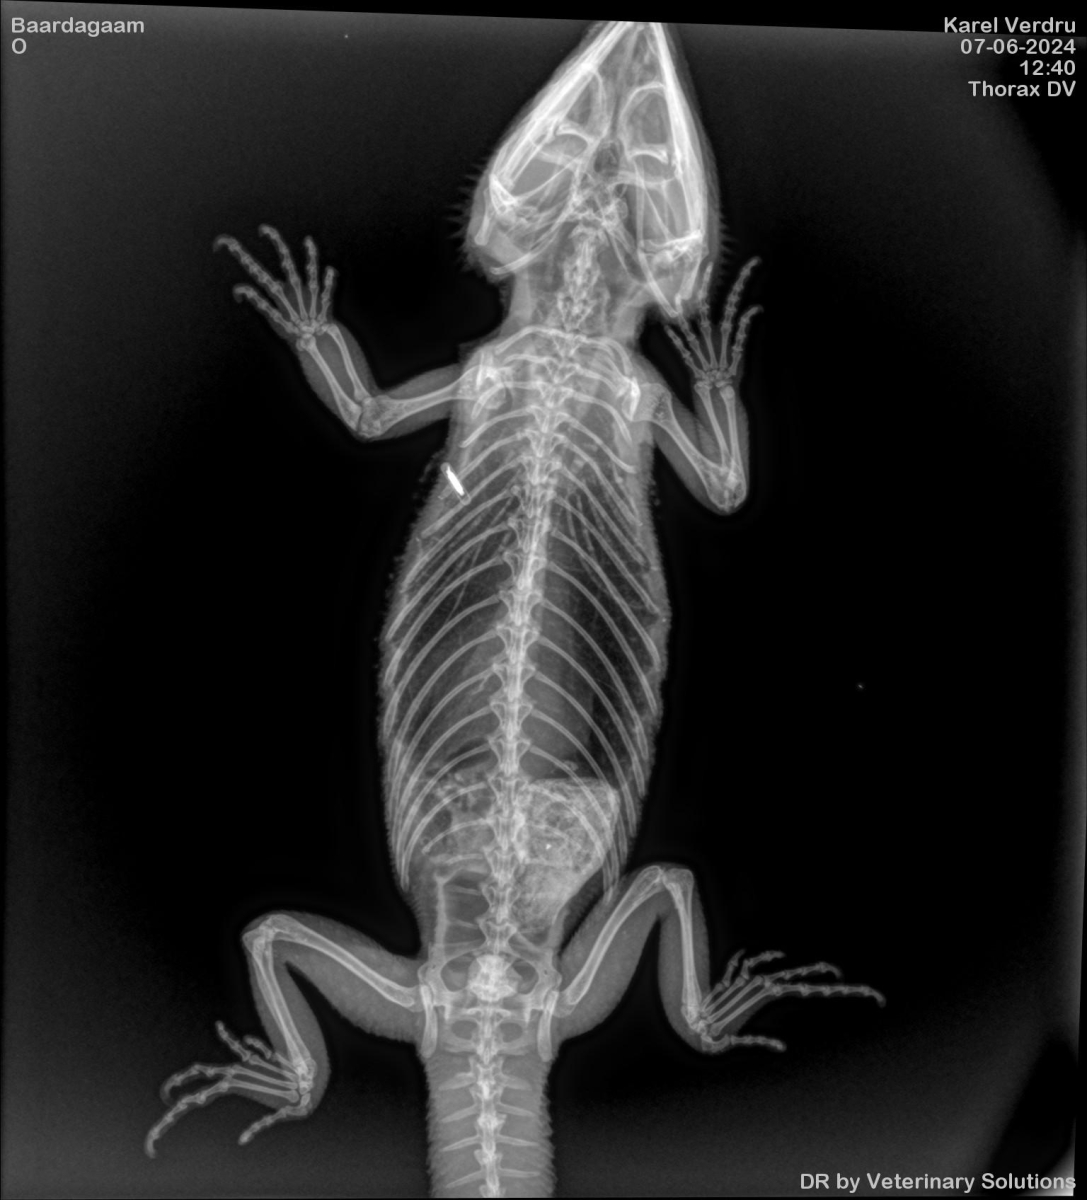

Onderzoek naar luchtwegproblemen en mestcontrole bij baardagaam Leonardo

Er was een vermoeden dat baardagaam Leonardo luchtwegproblemen had omdat hij vaak met de mond open zat. Daarom werden er röntgenfoto's genomen en werd er een keel-swab gedaan.

![]() |

Op de röntgenfoto's waren uraat-kristallen te zien. Deze worden veroorzaakt door een te hoog gehalte aan urinezuur. De uraatkristallen werden met behulp van een katheter en olie in de cloaca verwijderd.

Zowel Leonardo als soortgenoot Laura zagen er mager uit, dus er werd een mestonderzoek gedaan dat mogelijks duidde op coccidiose, een parasitaire infectie van de maag en het darmkanaal. Dit leidde tot de behandeling van alle dieren als voorzorgsmaatregel

Leonardo ziet er nog steeds slecht uit, vermoedelijk door een combinatie van parasieten en leverproblemen. Voorgaande medische behandelingen hebben tot nu toe niet geholpen, dus Leonardo zal buiten De Zonnegloed verder behandeld worden na een concrete diagnose.